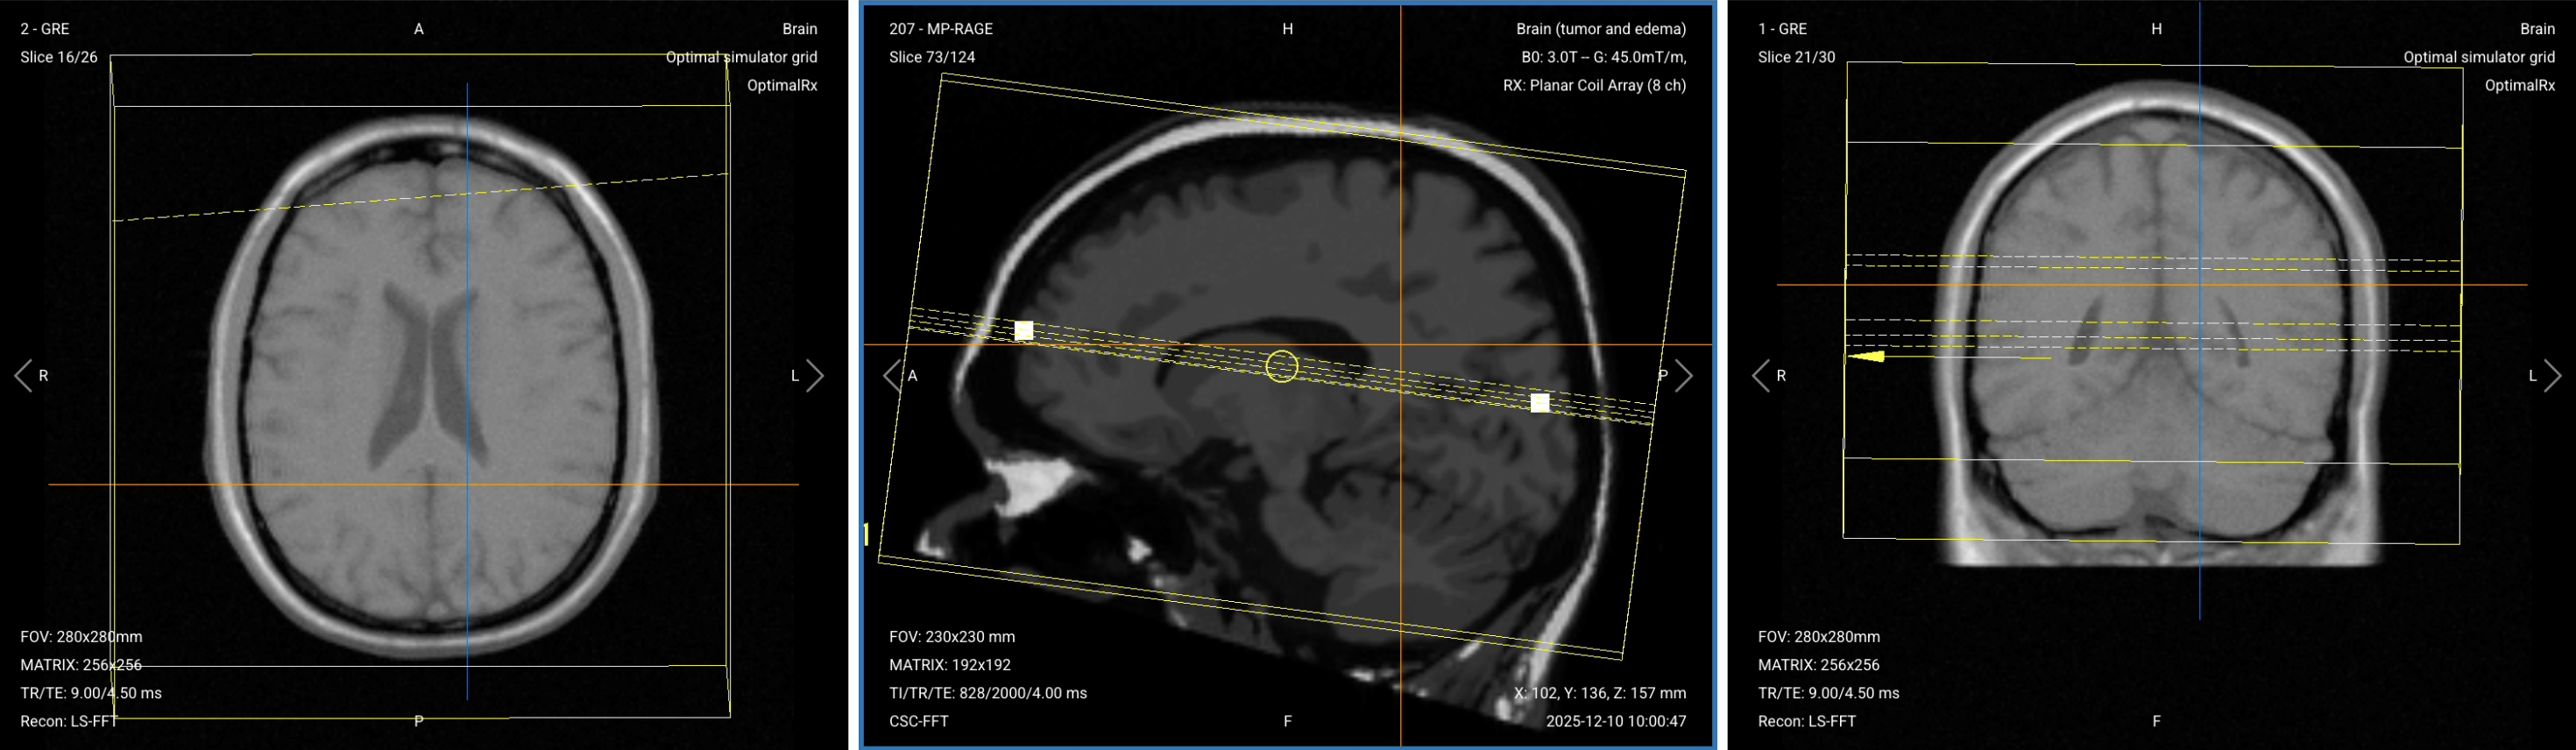

3. Capture the Initial Localizer Images

Before we can perform any MRI protocol, we must always capture initial localizer images of the patient. These images act as a guide for planning the detailed scans we will perform next.

We should always capture localizers in three planes:

1. Axial

2. Sagittal

3. Coronal

Once acquired, upload the initial localizer images into the three viewports.

Then, scroll through each of the image stacks to locate a central slice that clearly shows the anatomy of the brain.

Check that the localizers are aligned and that the head is well-positioned with no rotation. Most importantly, note if there are any previous surgical changes like a craniotomy or a shunt, and check for correct positioning in the isocenter.

Correct Setup of Localizer Images for Brain Tumor MRI:

Correct setup of localizer images for brain tumor MRI

1. Planning Sagittal T1 3D MP-RAGE (Pre-Contrast)

✅ Correct Planning:

Correct Planning Sagittal 3D T1 MP-RAGE (Pre-Contrast)

Planning Instructions:

• Use the mid-sagittal line as the anatomical reference.

• Align the slices as follows:

• Axial Localizer: Parallel to the mid-sagittal line.

• Coronal Localizer: Parallel to the mid-sagittal line running from the sagittal sinus through the third ventricle to the base of the skull.

• Use appropriate geometry parameters:

• Slice number: 128 or more to fully cover the brain from side to side with isotropic resolution.

• Slice thickness: 1–1.2 mm for isotropic voxels, providing equal resolution in all planes for multiplanar reconstruction.

• Slice gap: 0 mm (contiguous slices) for 3D acquisition.

• Set the fold-over direction (phase encoding) to anterior-posterior (AP) to keep the smallest field of view and reduce scan time.